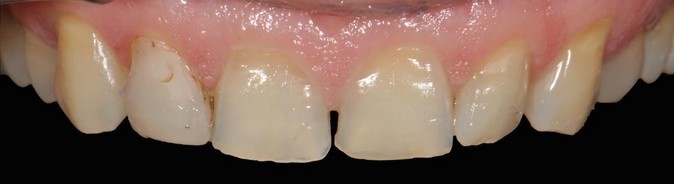

Тиунов Илья Игоревич: портфолио (19)

Имею международную сертификацию. Делаю лучшие виниры. Высокопрофессионально протезирую и реставрирую зубы. Работаю в комплексном подходе с командой специалистов: хирургом, терапевтом, гигиенистом и ортодонтом. Жизнь моя — публична. Работа — профессиональна. Намерения — серьезны. Ответственность — высока. Слог — краток.

Отбеливание зубов